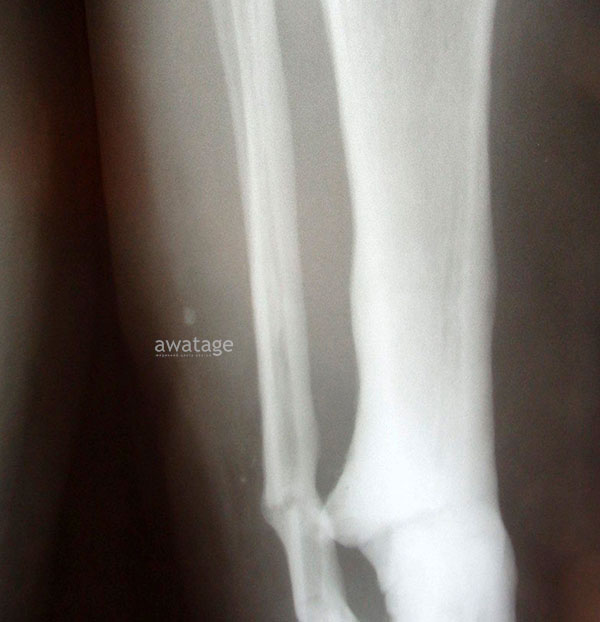

В целом, официальная медицина не признает эффективность УВТ при лечении остеомиелита. В медицинской литературе также не встречается такая информация. Несмотря на это в мед центре Аватаж уже есть клинические случаи успешного применения УВТ у пациентов с хронической формой данного заболевания, в том числе у пациентов, которые уже перенесли несколько оперативных вмешательств.

Лечение хронического остеомиелита методом ударно-волновой терапии (УВТ), пример которого смотрите по ссылке https://awatage.com/osteomyelitis-eswt/, является эффективным способом борьбы с заболеванием. Инновационная и отлично себя зарекомендовавшая техника позволяет добиться значительного улучшения состояния пациента за короткий период времени и снизить риск рецидивов.